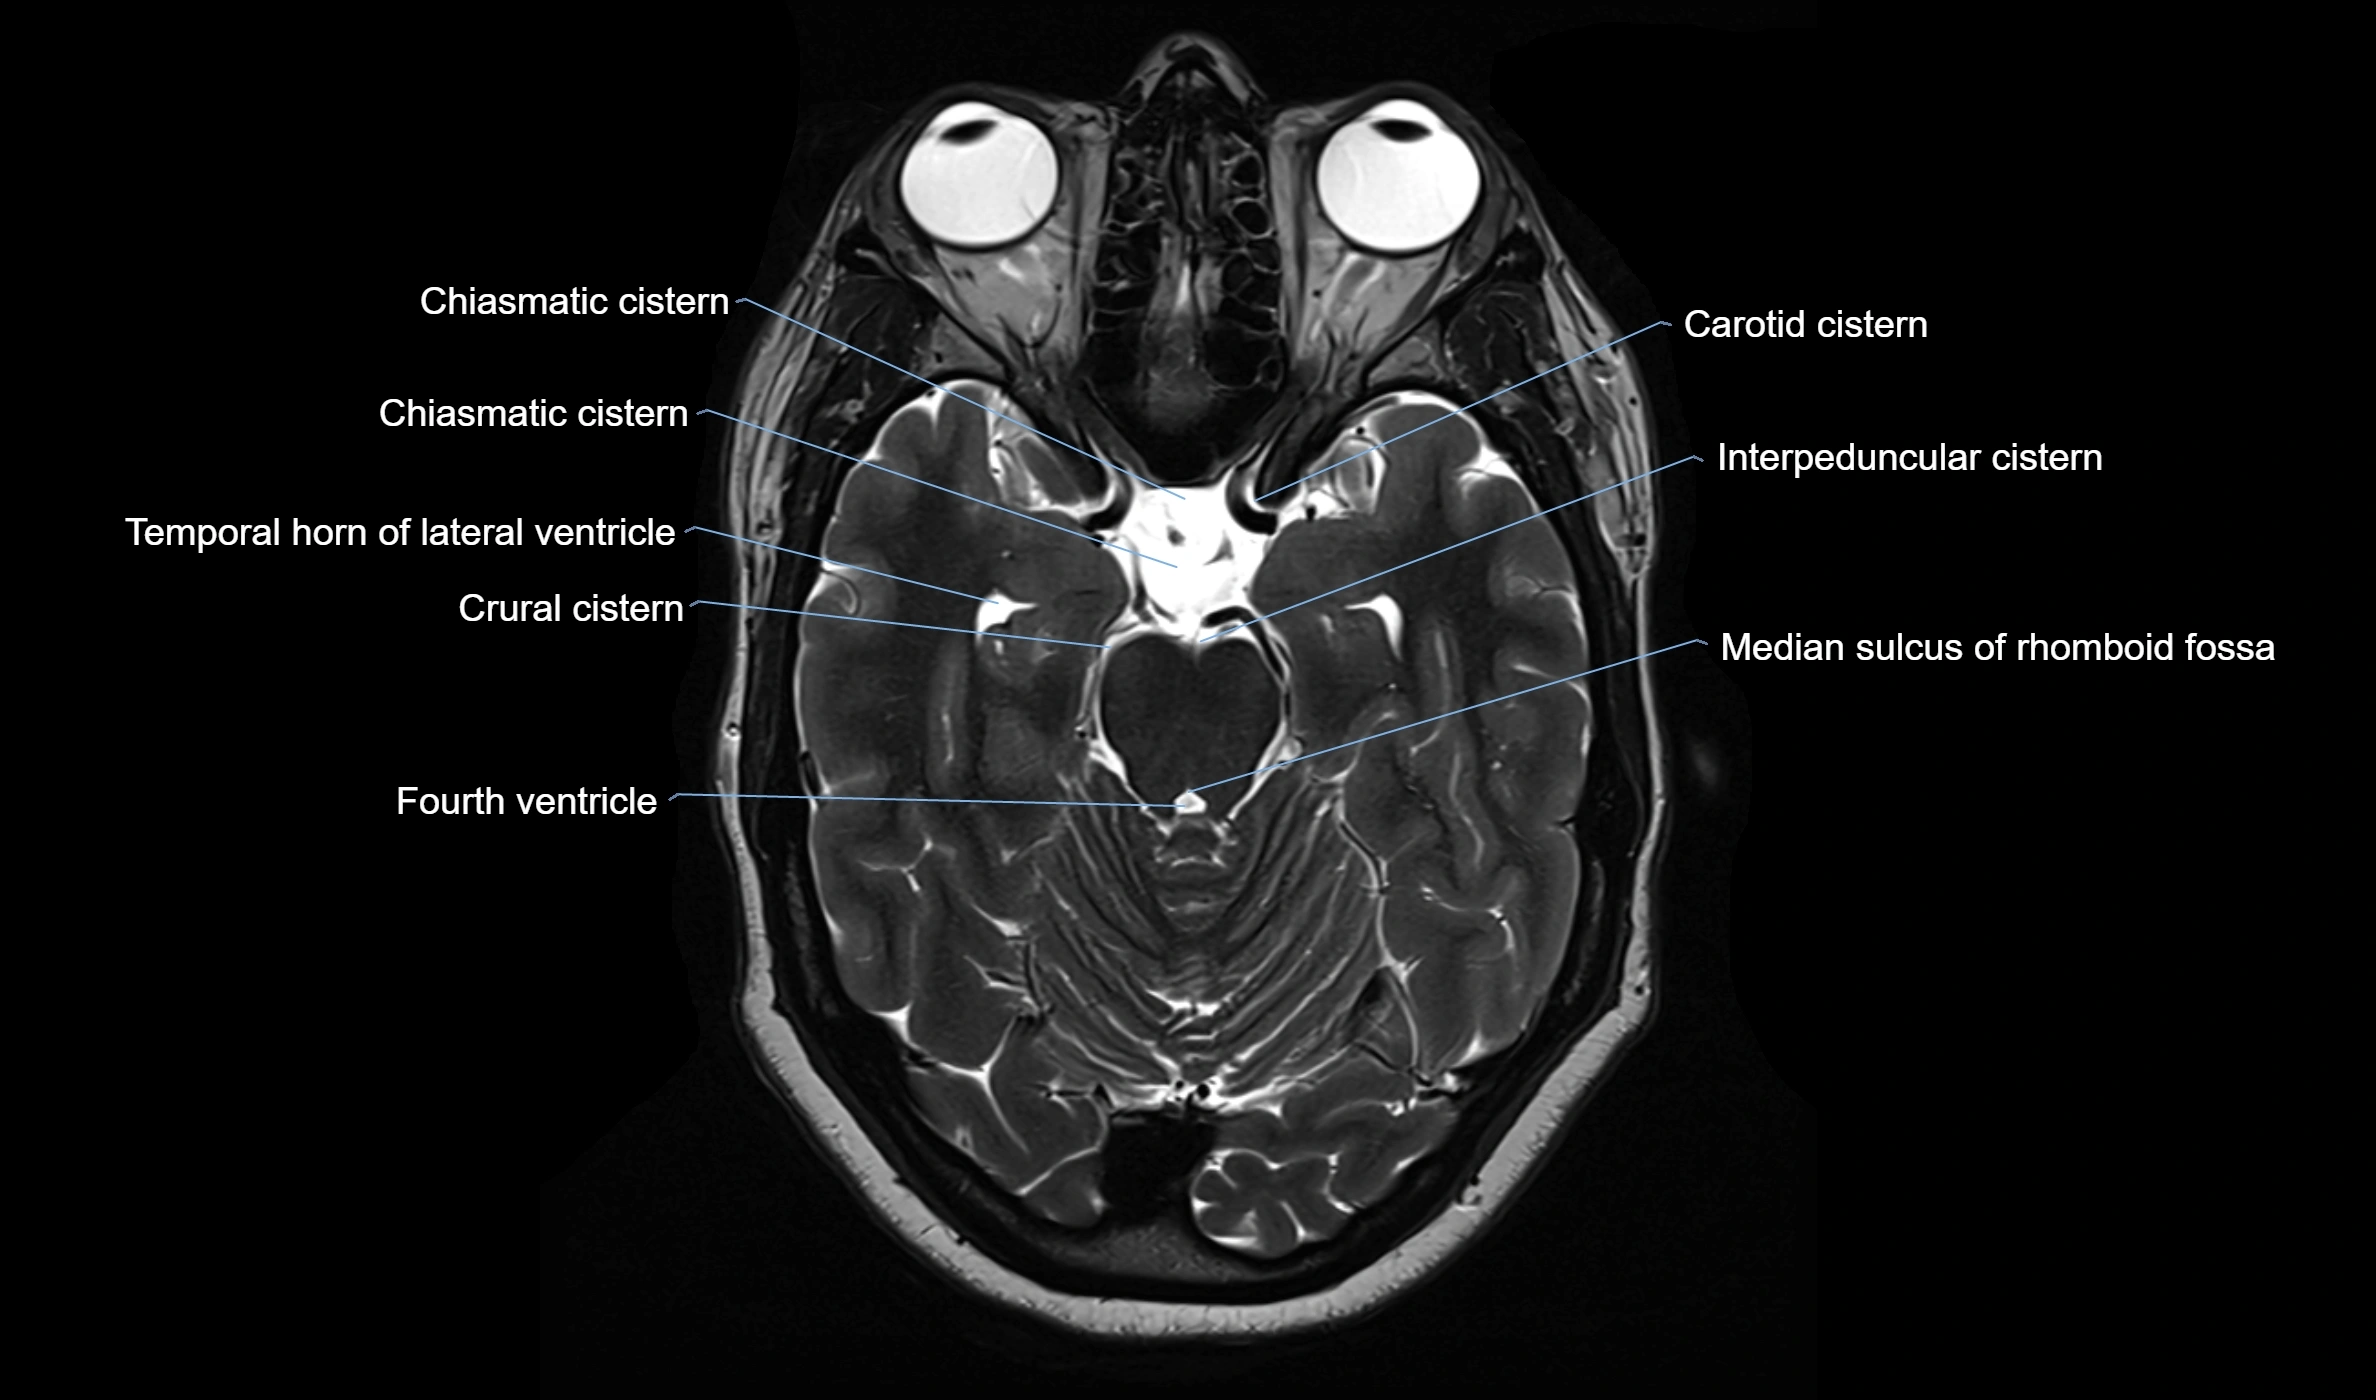

CT image

image